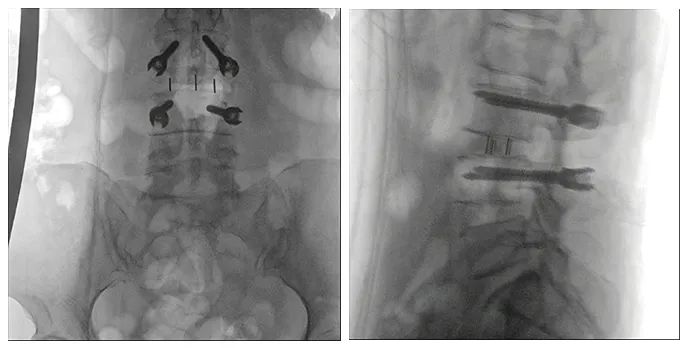

使用普愛醫(yī)療術(shù)中三維導(dǎo)航C臂進(jìn)行透視,根據(jù)透視影像引導(dǎo)確認(rèn)責(zé)任間盤、規(guī)劃手術(shù)方案,充分暴露骨組織,并通過(guò)專業(yè)器械切除椎板,暴露神經(jīng)及椎管;在C形臂的引導(dǎo)下,確定責(zé)任間盤上下椎體椎弓根位置,制定進(jìn)針點(diǎn)及進(jìn)針?lè)较颍刈倒较蛑踩爰怪葆斶M(jìn)行固定;放入椎間融合器,加固螺釘。最后再進(jìn)行C形臂透視,確認(rèn)手術(shù)的完成效果。

手術(shù)效果確認(rèn)